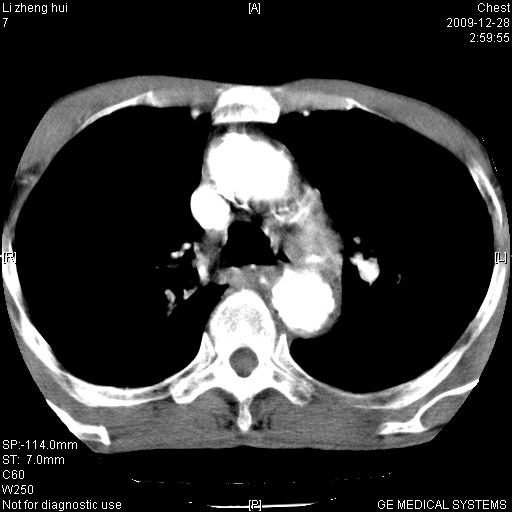

标题: CT23859:胸主动脉瘤

男  79岁 胸部痛急诊入院,晚上做的增强

考虑主动脉瘤?(增粗、钙化、壁血栓?)

动脉瘤伴附壁血栓

1)考虑胸主动脉壁间血肿或夹层动脉瘤。2)多发性肝囊肿。

1)考虑胸主动脉附壁血栓或夹层动脉瘤。2)多发性肝囊肿。